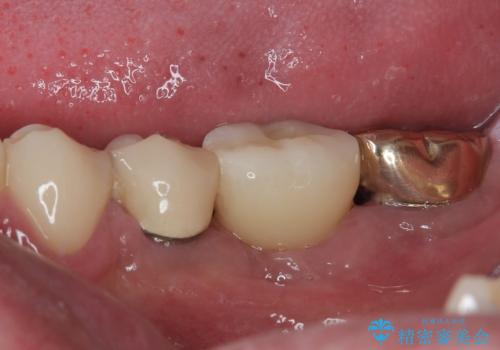

- 奥歯が割れてしまい、抜歯が必要となった患者様です。

以前にも歯が割れてインプラント治療を行いましたが、抜歯してからインプラント埋入→仮歯装着までに半年以上を要し、その間に残された歯への負担が大きくなり、セラミッククラウンが破折したことがありました。

そのため、当院に新しく導入した手法により、抜歯をした日にインプラントを埋入し、そのままを仮歯を装着することで、他の歯への負担を軽減する計画を立てました。